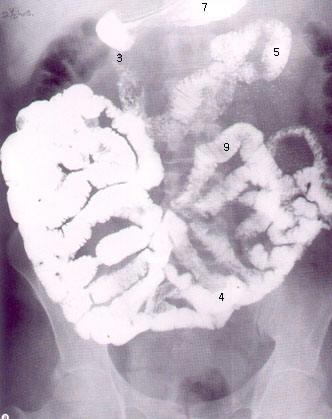

List: the organs of the GI tract in the sequence in which they occur starting with the mouth and ending at the anus (include the regions of each organ, ex: oropharynx and laryngopharynx of pharynx).

6.Small Intestine duodenum - jejunum - ileum - ileocecal valve/sphincter

9.Large Intestine cecum - ascending colon - transverse colon - descending colon - sigmoid colon - rectum - innner & outer anal sphincters